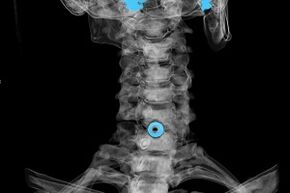

A diagnózist a jellegzetes tünetek alapján állítják fel, valamint a következőket alkalmazzák:

- röntgensugarak. A módszer hatástalan, különösen az osteochondrosis kialakulásának utolsó szakaszában.

- A nyaki gerinc MRI (mágneses rezonancia képalkotás). Olyan módszer, amely lehetővé teszi a csontszerkezetek, a porckorongsérv, azok méretének és fejlődési irányának megtekintését.

- Számítógépes tomográfia. Kevésbé hatékony megoldás, mint az MRI, mivel a sérvek jelenlétét és méretét nehéz meghatározni.